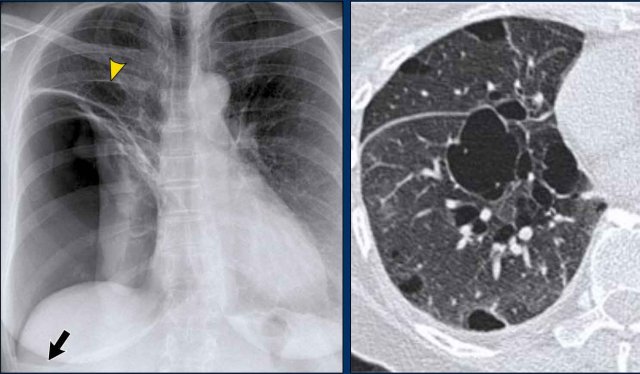

Hidden Areas (3): Pneumonia Below the Diaphragm

In this case, a pneumonia was primarily located below the right diaphragmatic dome (yellow arrow), within the posterior basal segment of the right lower lobe.

• On the lateral view, there is an increase in opacity over the lower thoracic vertebrae, indicating lower lobe consolidation (arrow).

• Again, image magnification may be necessary for adequate assessment.

Displacement of the Azygoesophageal Line (2) – Subcarinal Lymphadenopathy

A common cause of displacement of the azygoesophageal line is subcarinal lymphadenopathy (station 7).

On the chest X-ray, note superior displacement of the azygoesophageal line just below the carina, consistent with enlarged subcarinal lymph nodes (black arrow).

Additional right paratracheal lymphadenopathy is seen, displacing the right paratracheal stripe (white arrow) and deviating the trachea to the left.